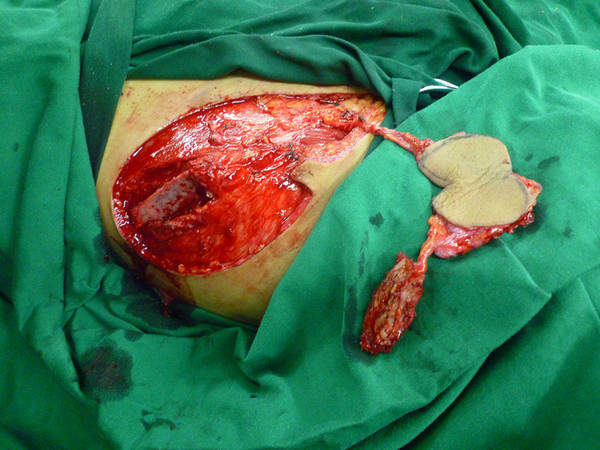

今天做的全型拇再造后供区修复的一种新方法

好久没发帖了,今天刚刚做的!供区是新的修复方式!谢谢讨论!

这个手术真是超爆!游离皮瓣还带髂骨!!!宗师级就是大宗师级!!!

您这手术真是游刃有余啊,您腹股沟皮瓣和骨瓣之间连接的那一个蒂是个穿支还是一个筋膜